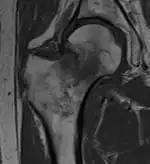

-

T1-weighted turbo spin echo MRI confirms a fracture, as the surrounding bone marrow has low signal from edema.